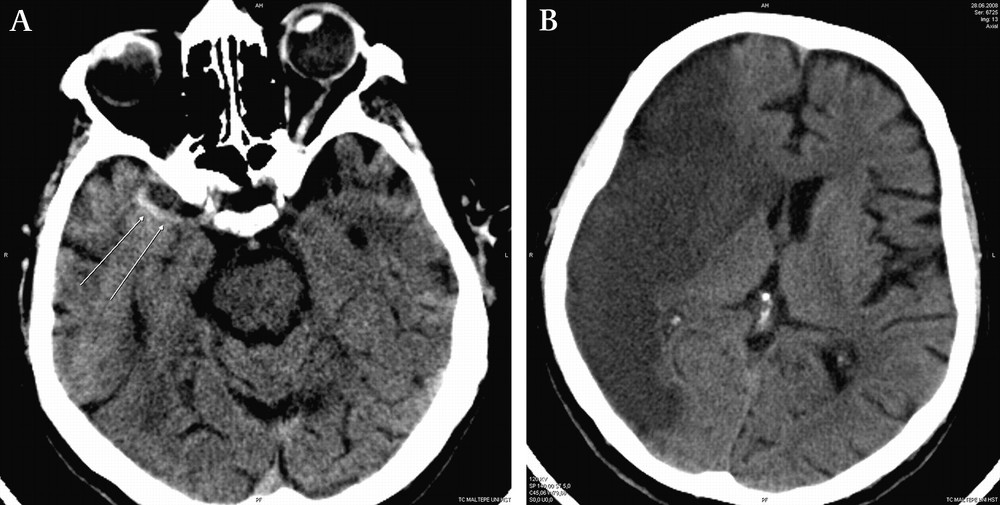

뇌경색은 뇌 혈관이 막혀서 일어나는 상황을 의미합니다. 이로 인해 뇌 조직이 손상을 입을 수 있습니다. "경색"이라는 용어는 혈액의 흐름이 차단되었다는 의미를 가지며, 이는 뇌의 영양을 공급하는 혈관에서 일어날 경우 심각한 문제를 초래할 수 있습니다.

뇌졸중이란 뇌 혈관에 문제가 생겨서 발생하는 질환을 일컫습니다. 이는 뇌출혈이나 뇌경색을 포함하며, 주로 뇌의 혈액 공급에 문제가 생겼을 때 발생합니다. 뇌졸중은 중대한 상황이며, 즉각적인 응급 처치가 필요합니다.